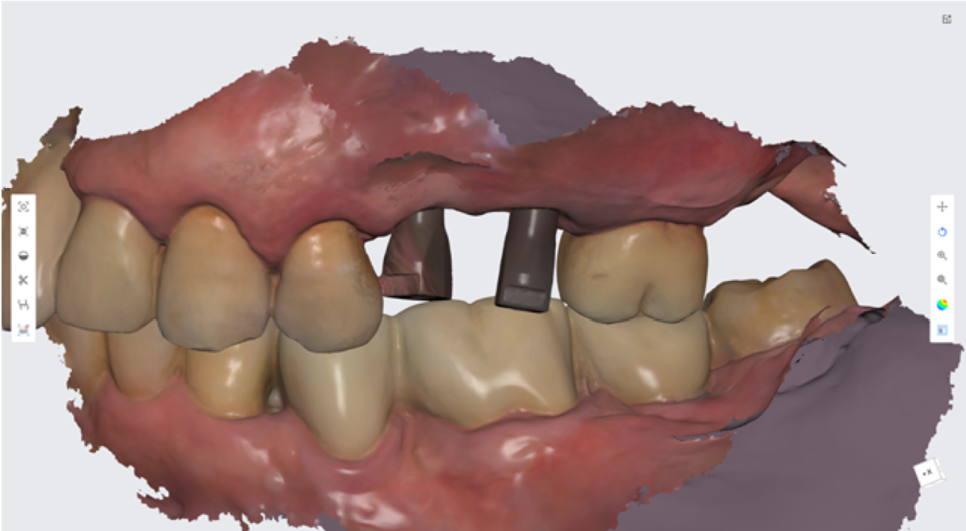

왼쪽 아래 임플란트 식립 수술 전,

중간확인차 전체 입안 사진 촬영을 하였습니다.

환자분은 오른쪽으로 식사는 잘 하고 계셨고,

왼쪽치료를 진행중인 상태입니다.

왼쪽 앞니의 경우에는,

오랜 염증으로 잇몸과 뼈가 많이 내려간 상태라 보철이 조금 길어지는 한계가 있었습니다...ㅠㅠ

컴퓨터로 스캐닝하는 프로그램을 사용하여

인상채득을 진행하였습니다.